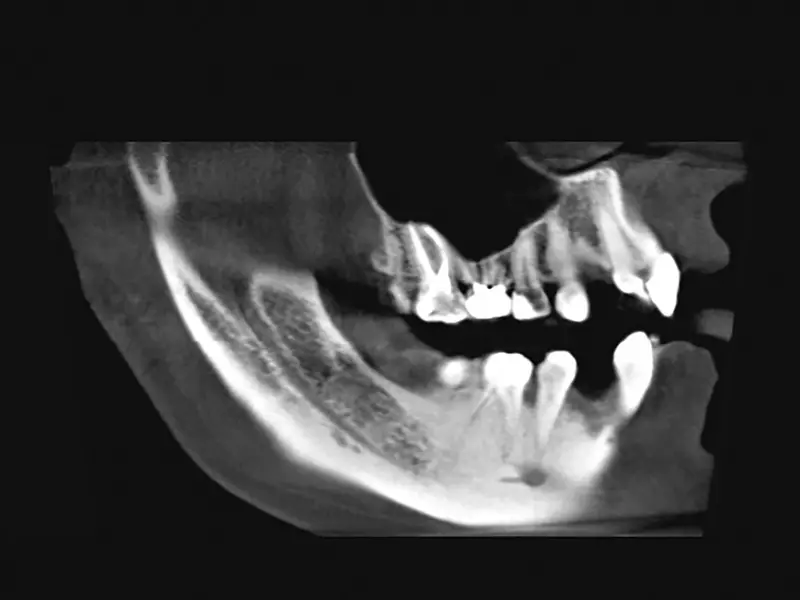

Pacjent, lat 19, leczony ortodontycznie. Ze względu na brak zawiązków zębów 12. i 22. zaplanowano leczenie implantologiczne. Biorąc pod uwagę ukształtowanie wyrostka zębodołowego w tych okolicach oraz możliwość powstania fenestracji wierzchołkowej w czasie wprowadzania implantów, przewidywano konieczność zastosowania materiału kostnego. Pacjent „dysponował” własnym materiałem kostnym w postaci dwóch zatrzymanych trzecich zębów trzonowych. Uznano, że ilość materiału pochodząca z jednego trzonowca będzie wystarczająca do zaopatrzenia obu miejsc implantacji.

Usunięto ząb 48., a następnie poddano go działaniu 3-procentowego roztworu wody utlenionej przez 3 minuty. Oczyszczono z włókien ozębnej, a następnie umieszczono na sucho w pojemniku, który był przechowywany w temperaturze 8°C do czasu zabiegu implantacji.

W dniu zabiegu ząb skruszono tak, aby uzyskać drobiny wielkości 800–1000 µm, które są optymalne dla procesu regeneracji kości. Po rozdrobnieniu otrzymano 1,5 cm³ materiału kostnego.